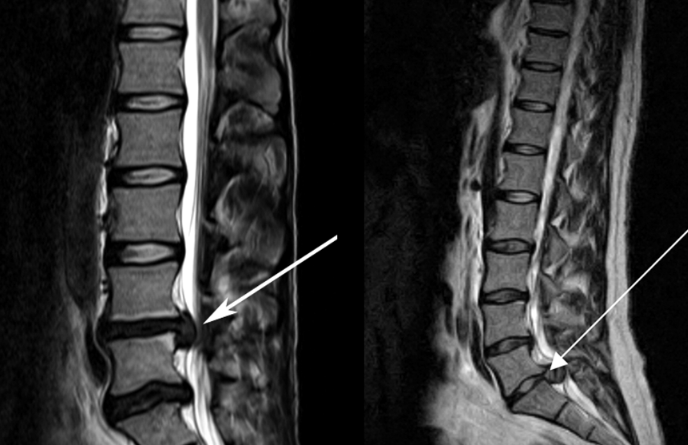

![]() 關于腰椎間盤突出 ![]() 腰椎間盤突出癥是纖維環破裂后髓核突出壓迫神經根造成以腰腿痛為主要表現的疾病。腰椎間盤退行性改變或外傷所致纖維環破裂,髓核從破裂處脫出,壓迫腰椎神經,從而出現腰腿放射性疼痛。 ![]() 病因: 一、退行性變: 目前認為,其基本病因是腰椎間盤的退行性變。退行性變是一切生物生、長、衰、亡的客觀規律,由于腰椎所承擔的特殊的生理功能,腰椎間盤的退行性變比 其他組織器官要早,而且進展相對要快。這個過程是一個長期,復雜的過程。所謂腰椎間盤退行性改變:即由于椎間盤受體重的壓迫,加上腰部又經常進行彎曲、后伸等活動,易造成椎間盤的擠壓和磨損,尤其是下腰部的椎間盤,從而產生退行性改變。腰椎間盤退行性改變是本病發生的基礎。 二、其他因素: 1、外力作用:在日常生活和工作中,部分人往往存在長期腰部用力不當、過度用力姿勢或體位的不正確等情況。例如長期從事彎腰工作的煤礦工人和建筑工人需經常彎腰提舉重物。這些長期反復的外力造成的損傷日積月累地作用于椎間盤,加重了退變的程度。 2、椎間盤自身解剖因素的弱點: (1) 椎間盤在成人之后逐漸缺乏血液循環,修復能力也較差,特別是在退變產生后,修復能力更加微弱。 (2) 椎間盤后外側的纖維環較為薄弱,而后縱韌帶在腰5、骶1平面時寬度顯著減少,對纖維環的加強作用明顯減弱。 (3) 腰骶段先天異常:腰骶段畸形可使發病率增高,這些異常造成椎間隙寬度不等,并常造成關節突出,關節受到更多的旋轉勞損,使纖維環受到的壓力不一,加速退變。 3、種族、遺傳因素:有色人種發病率較低,例如印第安人和非洲黑人等發病率較其他民族明顯要低。 ![]() 2 病理 腰椎間盤突出癥的病理變化過程大致可分為三個階段: 1、突出前期:髓核因退變和損傷可變成碎塊狀物,或呈瘢痕樣結締組織,變性的纖維環可因反復損傷而變薄變軟或產生裂隙。此期病人可有腰部不適或疼痛,但無放射性下肢痛。也有的人原無病變,可因一次大的暴力引起髓核突出。 2、突出期:外傷或正常的活動使椎間盤壓力增加時,髓核從纖維環薄弱處或破裂處突出。突出物刺激或壓迫神經根即發生放射性下肢痛,或壓迫馬尾神經發生大小便功能障礙。在老 年患者,可因椎間盤退變,整個纖維環變得軟弱松弛,椎間盤可呈彌漫性向周圍膨出。 3、突出晚期:腰椎間盤突出后,病程較長者,椎間盤本身和其他鄰近結構均可發生各種繼發性病理改變。 3 誘發因素 腰椎間盤突出癥的基本因素是椎間盤退變,但某些誘發因素可致使椎間隙壓力增高,引起髓核突出。此種誘發因素常與以下因素有關: 1. 年齡因素:腰椎間盤突出癥的好發年齡在30-50歲,平均手術年齡在40歲,因此退變可能是其重要因素。 2. 身高與性別:有人認為身材過高也會易發腰突癥,而男性發病率是女性的5倍。 3. 增加腹壓:臨床上有約1/3的病人在發病前有明確的增加腹壓的因素,如劇烈的咳嗽、噴嚏、屏氣、用力排便等。使腹壓增高,破壞了椎節與椎管之間的平衡狀態。 4. 不良體位:人在完成各種工作時,需要不斷更換各種體位以緩解腰部壓力,如長期處于某一體位不變,即可導致局部的累積性損傷。特別是長期處于不良姿勢更容易誘發本病。 5. 職業因素:重體力勞動者發病率最高,白領勞動者最低。汽車駕駛員由于長期處于顛簸和振動狀態,椎間盤承受的壓力大且反復變化,也易誘發椎間盤突出。 6. 受寒受濕:寒冷或潮濕可引起小血管收縮、肌肉痙攣,使椎間盤的壓力增加,可能造成退變的椎間盤破裂。 ![]() ![]() ![]() ![]() 癥狀: 腰椎間盤突出癥患者最多見的癥狀為疼痛,可表現為腰背痛、坐骨神經痛,典型的坐骨神經痛表現為由臀部、大腿后側、小腿外側至跟部或足背的放射痛。據臨床統計,約95%的腰突癥患者有不同程度的腰痛,80%的患者有下肢痛。特別是腰痛,不僅是腰椎間盤突出最常見的癥狀,也是最早出現的癥狀之一。 ![]() ![]() ![]() 檢查: 1、X線:腰椎間盤所包括的髓核、纖維環和軟骨板密度均較低,在X線下并不顯影,因此臨床上腰突癥患者的腰椎X線平片可僅有一些非特異性的變化,甚至無異常變化。因此單純腰椎平片并不能作為有無腰椎間盤突出癥的直接依據,但X線能發現腰椎的退行性改變和結構異常,對提示椎間盤的退變有重要意義,并且能排除其他的一些腰椎疾患,如腰椎結核、腫瘤和腰椎滑脫等。典型的腰椎間盤突出癥患者通過病史、體征和X線平片即能作出初步的診斷。 2、CT檢查:腰椎的CT可以清楚地顯示椎間盤突出的部位、大小、形態和神經根、硬脊膜受壓的情況,同時還可顯示黃韌帶肥厚、小關節增生、椎管和側隱窩狹窄等情況。對腰椎間盤突出癥診斷的準確率達到80%-92%。 3、核磁共振(MRI):核磁共振沒有輻射,可以多方位成像(橫斷面、冠狀面、矢狀面和斜面),對解剖細節顯示較好,對組織結構的細微病理變化更敏感(如骨髓的浸潤),可以排除神經和脊柱腫瘤等。對于一些落到椎管的髓核組織也不會遺漏。 4、脊髓造影:脊髓造影利用椎管內蛛網膜下腔的空隙,注入造影劑后在X線下攝片,顯示椎管內部結構。目前常用水溶性造影劑,能較清晰地顯示硬膜腔、馬尾神經和神經根鞘,對腰椎間盤突出癥的診斷可達90%左右,主要X線表現為硬膜囊壓迫征象和神經根鞘壓迫征象。但由于CT和MRI在臨床的廣泛應用,無創傷且診斷率更高,脊髓造影在臨床上的應用已經大大減少,而且由于它副作用較大,甚至可能造成截癱等嚴重情況,目前主張慎重選用。 5、肌電圖:肌電圖是對周圍神經與肌肉的電生理檢查方法,可用于觀察并記錄肌肉在靜止、主動收縮和支配其的周圍神經受刺激時的電活動,同時也可用來測量周圍神經的傳導速度。在腰椎間盤突出癥上,肌電圖主要通過檢查雙下肢肌肉的興奮性來反映相應神經根的狀態,并根據異常電活動的分布范圍來判斷椎間盤突出和神經根受壓的節段。在脊神經根和馬尾神經受壓的病人,肌電圖陽性率可達80%-90%,但與CT和MRI相比并不是首選的檢查手段,可用于輔助診斷和判斷神經根的受壓情況,同時也可以用來作為判斷治療后神經根恢復情況的指標之一。 ![]() ![]() ![]() 預防: 腰椎間盤突出癥是在退行性變基礎上積累傷所致,積累傷又會加重椎間盤的退變,因此預防的重點在于減少積累傷。 日常注意事項: 1.平時要有良好的坐姿,睡眠時的床不宜太軟。 2.長期伏案工作者需要注意桌、椅高度,定期改變姿勢。 3.職業工作中需要常彎腰動作者,應定時伸腰、挺胸活動,并使用寬的腰帶。 4.應加強腰背肌訓練,增加脊柱的內在穩定性,長期使用腰圍者,尤其需要注意腰背肌鍛煉,以防止失用性肌肉萎縮帶來不良后果。 5.如需彎腰取物,最好采用屈髖、屈膝下蹲方式,減少對腰椎間盤后方的壓力。 ![]() ![]() ![]() 治療: (一)中醫外敷療法: 腰椎間盤突出可以外貼 腰突正骨膏,其有效成分可透入皮膚產生活血,止痛,化淤,通經走絡,開竅透骨,祛風散寒等效果,并通過藥物的歸經作用而調理機體陰陽平衡,滲透于表皮,刺激神經末梢,促進局部血液微循環,扶正固本、改善體質,從根本上、全方位針對腰椎疾病病機特點而發揮療效,改善病變周圍組織營養,起到修復骨病組織的作用,最終達到治療目的。 (二)自我治療: 1.腹肌鍛煉: 也就是仰臥起坐。每次做十個,每天三次。(可根據患者的體質來定,不可逞強)。 2.交叉扭腰: 兩腳分開與肩寬,腳尖向內兩臂伸直,一手在體側,一 手舉過頭頂。如果右手在上,先向左側后方擺。左側相反。于此同時腰部也隨之扭動,左右各100次。 3.抱膝觸胸: 處于仰臥位,雙膝屈曲,手抱住膝部,使盡量靠近胸部,然后放下,一上一下為一個動作,可持續30個。 4.腰背肌鍛煉: 處于平臥,雙膝彎曲放在床上,然后用力將臀部抬起,離開床面10厘米。這時您會感覺到腰背部在用力,堅持5秒鐘,反復10下。 ![]() (三)非手術治療: 非手術療法是治療腰椎間盤突出癥的基本療法,約80%以上的患者經保守治療均可得到緩解和痊愈。其主要療法有: 1.日常家庭治療:早期腰椎間盤突出癥,癥狀輕微,不需要做特殊的治療。第一,注意臥床休息,避免腰椎受外力壓迫,第二,應用其他方法積極鍛煉腰部肌肉力量。 2.牽引治療; 3.推拿按摩治療; 4.物理治療; 5.消炎鎮痛藥物; 6.減輕神經根水腫藥物。 (四)推拿治療: 1.解除腰臀部肌肉痙攣 2.拉寬椎間隙,降低盤間壓力 3.增加椎間盤外壓力 4.調整后關節,松解粘連 5.促使受損傷的神經根恢復功能 (五)微創治療: 微創治療方法的目的是消除腰椎間盤突出的髓核以解除對神經的壓迫。微創治療技術采用可視設備,創口不足一厘米有些甚至不足一毫米。消融或摘除髓核,從根本上解除致病因素,因而能夠取得很好的效果。 (六)手術治療: 腰椎間盤突出癥的手術原則是嚴格無菌操作,盡量保留不必去除的骨結構和軟組織結構,以最小的創傷達到足夠的顯露,仔細徹底地去除病變組織,達到治療目的。 ![]() ![]() 綠柏相關產品: ![]() 懸吊訓練療法是康復醫學中以持久改善肌肉骨骼疾病為目的的,應用主動治療和訓練的一個總的概念整合,是一種運動感覺的綜合訓練系統,包括診斷與治療兩大系統。 產品特點: 1.電腦軟件管理系統,涵蓋患者信息管理、評估、訓練、量表、報告、視頻教學六大模塊,輕松實現評估與訓練一體化管理; 2.多點多軸設計,滿足不同治療方案設計; 3.懸吊工作站及各個懸吊點,均能實現任意位置移動,一鍵解鎖,省時省力; 4.實時力反饋,精準量化弱鏈測試及懸吊治療全過程,給治療師及患者最直觀的效果呈現; 5.智能神經肌肉促通裝置,可根據評估結果設置治療模式、頻率、時間等相關參數,讓懸吊康復更加高效有針對性; 6.外觀高端大氣,結構穩固,給患者安全保障,增加治療信心。 ![]() |